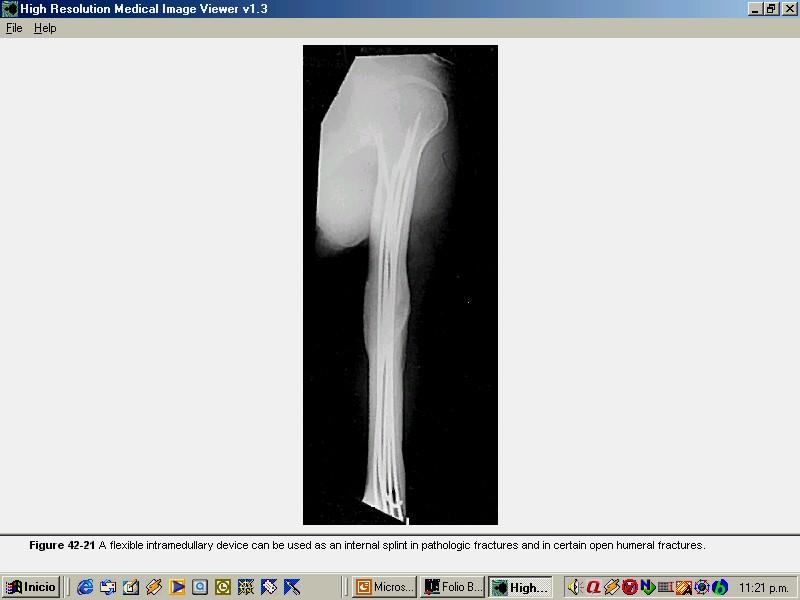

FRACTURAS 1/3 PROX DE HUMEROFRACTURAS 1/3 PROX DE HUMERO ENCLAVADO ENDOMEDULAR RETROGRADO. ENCLAVADO ENDOMEDULAR RETROGRADO. ENCLAVADO ENDOMEDULAR FLEXIBLE. Tipo Ender. ENCLAVADO ENDOMEDULAR FLEXIBLE. Tipo Ender.